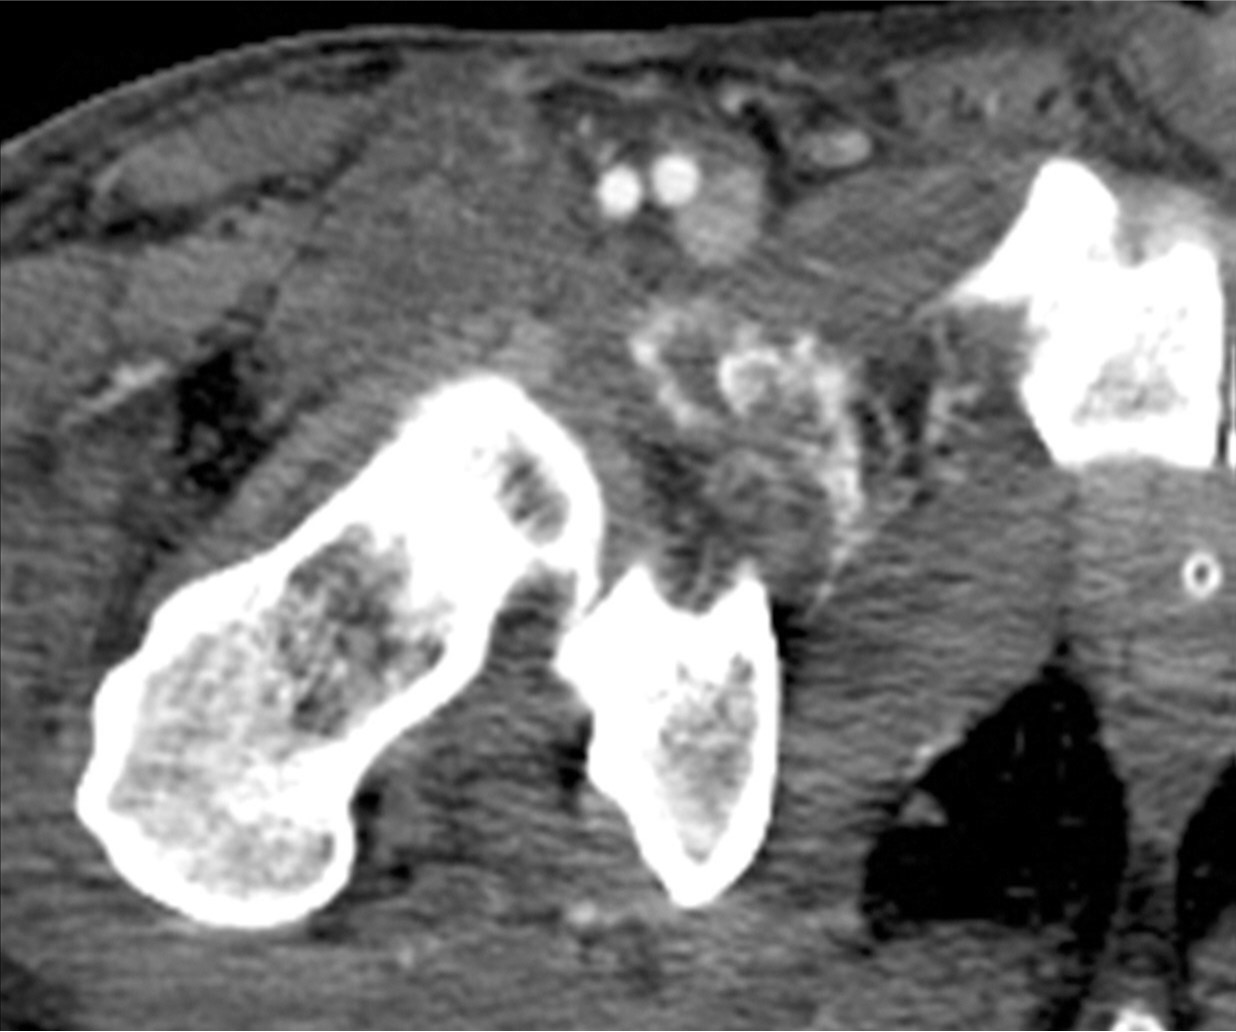

Fig. 4. B

Fig. 4A, B. On Doppler US (A) immediately after thrombin injection, there is no color swirl, indicating disappearance of pseudoaneurysm. On CT scan (B) obtained two days after thrombin injection, there is no visible pseudoaneurysm.